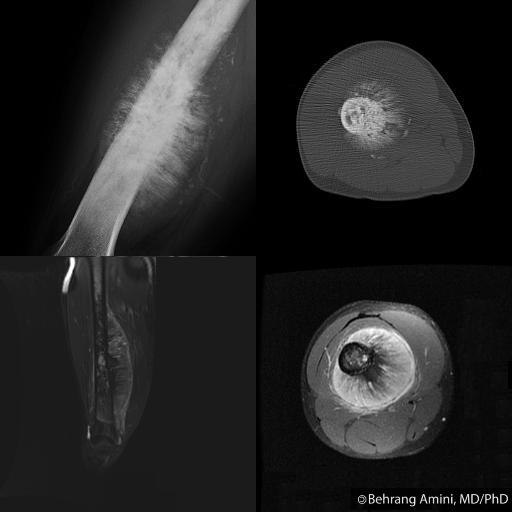

9 widespread or generalized periosteal reaction What Is Periosteal Reaction Periosteal reaction refers to the elevation of periosteum from cortical bone and the subsequent deposition of new bone in this space. Periosteal reaction typically involves the long bones, particularly the tibial and fibular diaphyses. Solid periosteal pattern is thought to evolve from single layer and multilayered periosteal reactions, forming a solid layer of mature new bone adjacent to the cortex.. What Is Periosteal Reaction.